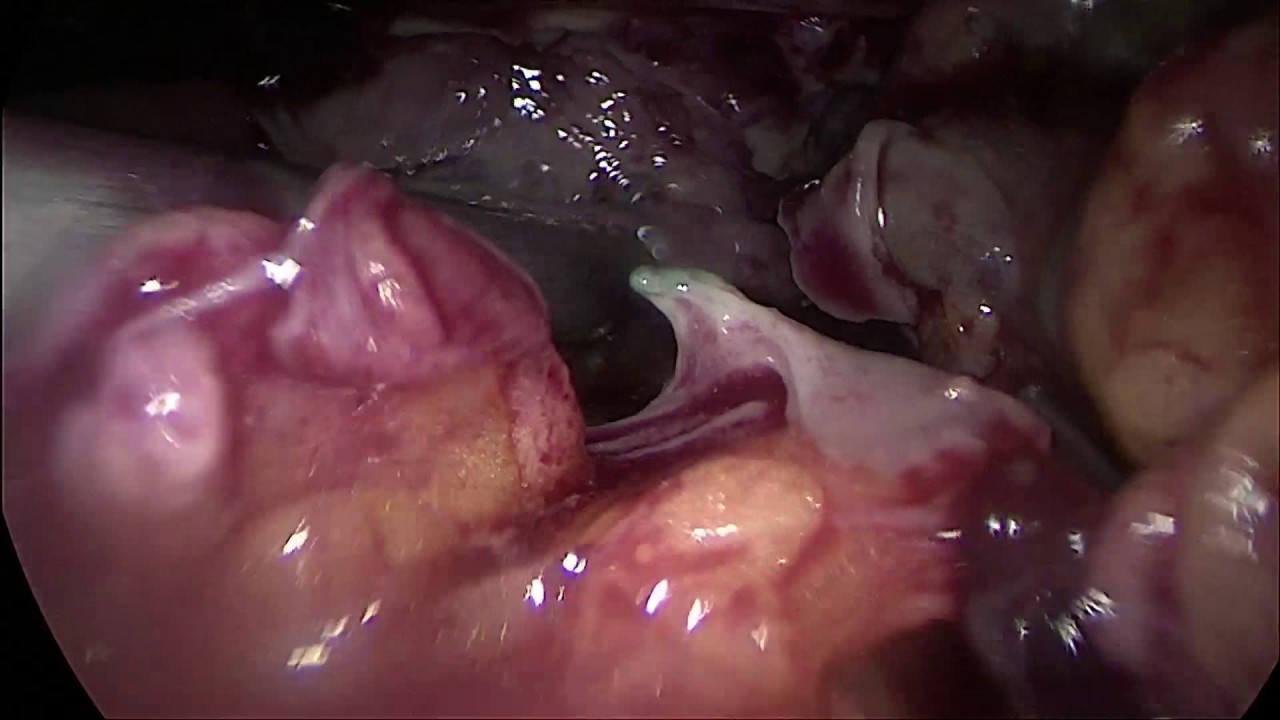

Akademik kariyerine 2016 yılında İstanbul Okan Üniversitesi Tıp Fakültesi Genel Cerrahi Anabilim Dalı’nda öğretim üyesi olarak başlayan Dr. Ferhatoğlu, 2020 yılında İstanbul Okan Üniversitesi Hastanesi Organ Nakli Kliniği’nde sorumlu yardımcı uzman olarak atanmıştır. Dört yıl süresince sürdürdüğü bu görevinde 400’ün üzerinde böbrek nakli operasyonunu başarıyla gerçekleştirmiştir.

Abdominal Laparoskopi

Laparoskopi

Laparoskopik Cerrahi